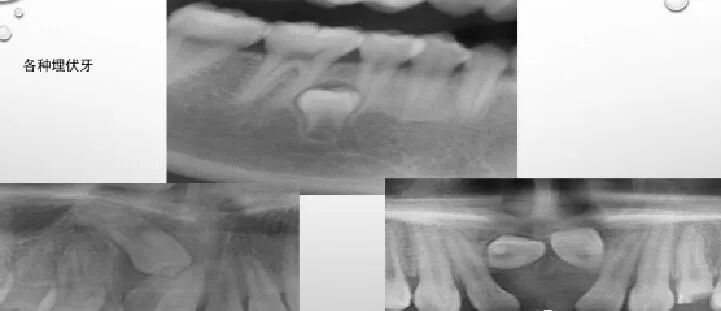

牙髓疾病 dental pulp disease:

牙内吸收

曲面断层片怎么看正畸【曲面断层片(全景片)】如何解读和查看:牙周?牙体?牙髓?关节?_https://www.jmylbn.com_新闻资讯_第4张

患牙髓腔扩大,呈圆形/卵圆形/不规则形密度减低透射影。发生于根管者有长短不一、粗细不均、沿根管的扩大影。髓室壁或根管壁变薄。可伴有根尖吸收/感染/折断。

牙髓钙化

曲面断层片怎么看正畸【曲面断层片(全景片)】如何解读和查看:牙周?牙体?牙髓?关节?_https://www.jmylbn.com_新闻资讯_第5张

阻射影;后牙为圆形、卵圆形,可游离于髓室内,也可附着于髓室壁;前牙为条状或针状,充满于髓室或根管内,周围有线状低密度影像环绕。

曲面断层片怎么看正畸【曲面断层片(全景片)】如何解读和查看:牙周?牙体?牙髓?关节?_https://www.jmylbn.com_新闻资讯_第6张

正常髓室及根管影像完全消失,不能辨别出髓腔界线,有的尚可见,但很细。